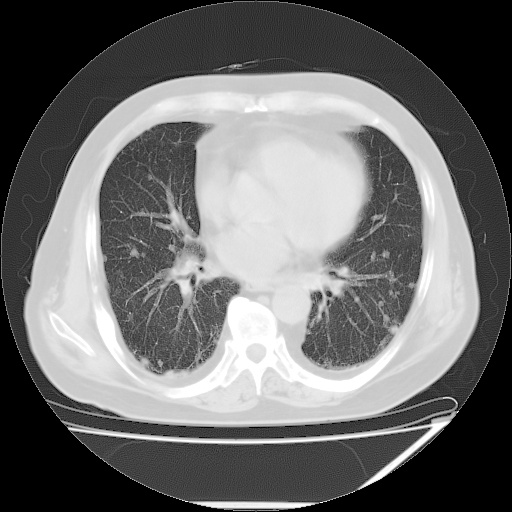

患者,男51岁,反复咳嗽多年,加重10余天,自觉精神不振,无发热,无尿频、尿急及排尿不畅,最近体重有减轻(具体不祥),化验:血常规正常,血糖正常,转氨酶不高,乳酸脱氢酶轻度增高(具体记不得了)

双肺多发结节影,以肺周围分布较多,纵隔淋巴结肿大,考虑双肺转移瘤可能性大。

双肺多发结节影及纵隔内可见肿大淋巴结考虑双肺及纵隔淋巴结转移,建议进一步检查原发灶

1.双肺散在分布小结节影 气管旁淋巴结肿大 中叶背部有胸膜增厚胸膜反应 双侧胸腔积液 考虑转移性肺癌

本例的特点:结节弥漫多发,但所有的结节都没有一个比较清楚的境界,其边界都比较模糊;

其分布并不像转移瘤那样主要分布于肺的外围,而是中心部位较外围的要多;

印象:把炎症性病变放在首位;

考虑 1、慢支并感染; 2、转移待排----右下肺那个有小泡的要小心一些;

建议正规抗炎两周后复查;如有条件请查肿瘤系列;